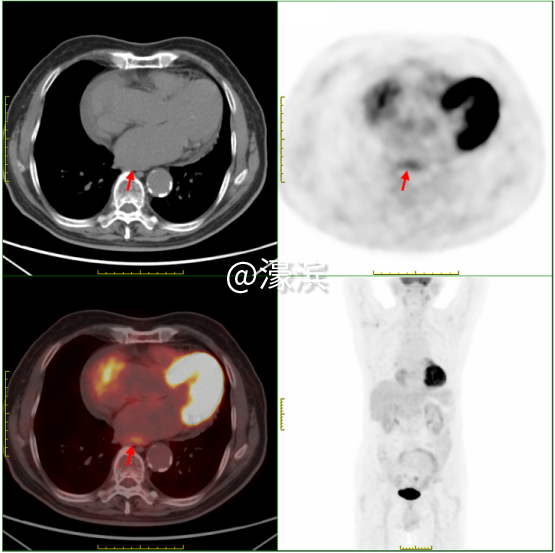

①食管癌精准定位 发现食管下段1.3cm管壁增厚伴FDG代谢增高(SUVmax 3.1),与病理结果高度吻合,为后续手术或放疗提供精准靶区定位。 ②全身隐匿病灶"无处遁形" 鉴别颈部炎性淋巴结(SUVmax 4.2)与转移灶,避免过度治疗;发现双肾囊肿(最大3.6cm)、肝囊肿等良性病变,完善全身健康评估;识别牙槽根周炎症(SUVmax 10.9)、上颌窦炎等感染灶,指导抗炎治疗。 ③全身健康"全景扫描" 同步检出肺气肿、冠脉钙化、前列腺增生伴钙化等退行性病变,精准锁定多处微小病灶,为多学科诊疗提供完整数据支持。 "对于SUVmax<2.5的病灶,如本例患者的食管癌灶,我们也能通过双能谱CT物质分离技术,识别早期癌变的特征性脂质成分变化。"瑞慈医院医学影像科核医学组主任夏淦林提到,"PET-CT不是简单的影像设备,而是现代精准医疗的决策中枢,精准捕捉到<1cm的微小病灶。" 选择瑞慈PET-CT的四大理由?  (一)美国GE进口超高清设备:高灵敏度、高清晰度、高分辨率、高扫描速度、高精准定量测量 (二)专业影像科团队:从业20余年的“南通PET-CT第一人”领衔解读诊断报告 (三)检查快速高效:提前一天预约即可检查,检查后最早当天下午出报告,最晚第二天上午出报告。 (四)星级检查环境:独立贵宾休息室,隐私零干扰、全流程单向通行,动线设计更科学。 PET-CT主要解决哪些问题? PET-CT在肿瘤方面的应用占其床应用的90%以上。 主要适应症如下: 协助诊断 ·对肿瘤高危人群,早期发现或排除肿瘤; ·对肿瘤标志物高或副肿瘤综合征患者,寻找肿瘤病灶所在; ·对已发现可疑病变者,鉴别良、恶性; ·对可疑肿痛患者,指导选择活检部位; ·对已发现肿瘤转移者,寻找原发灶。 指导治疗 ·对恶性肿瘤患者,进行更准确分期,全面了解全身病变情况; ·肿瘤恶性程度分级和预后判断; ·指导放疗计划靶区的设定。 疗效评估和复发监测 ·肿瘤治疗效果的评估; ·肿瘤残存病灶与坏死、纤维化组织的鉴别; ·肿瘤治疗后标志物仍高或重新升高,寻找残存、复发或转移病灶; ·肿瘤复发的监测。